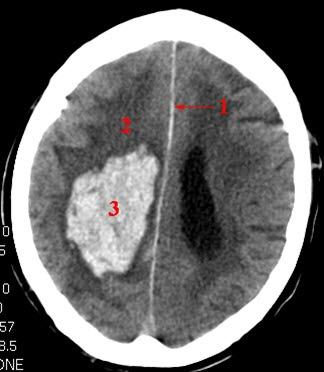

CT axialbilde uten kontrast

Blødning (lyst område) i hjernen på pasientens høyre side (CT bilder av hjernen vises normalt nedenfra og opp, pasientens ansikt peker oppover). Det er lite ødem og ingen overskyvning av midtlinjestrukturene

- Falx cerebri

- Ødemsone

- Blødning